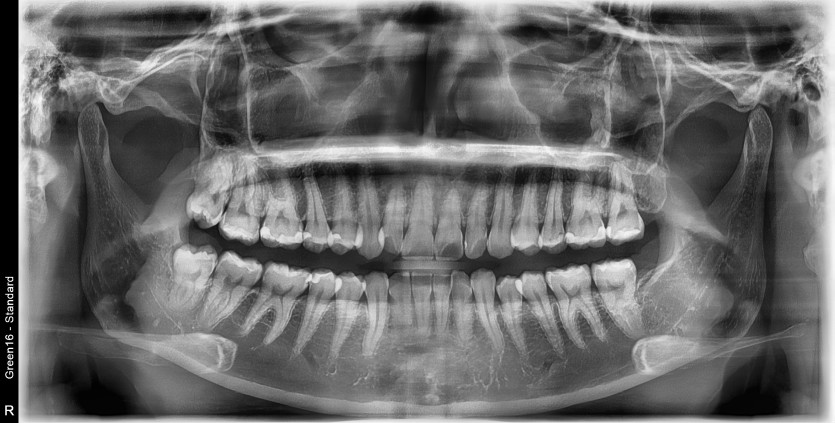

#18,48 사랑니 발치

구강 외과 전문의가 당일 발치했습니다.